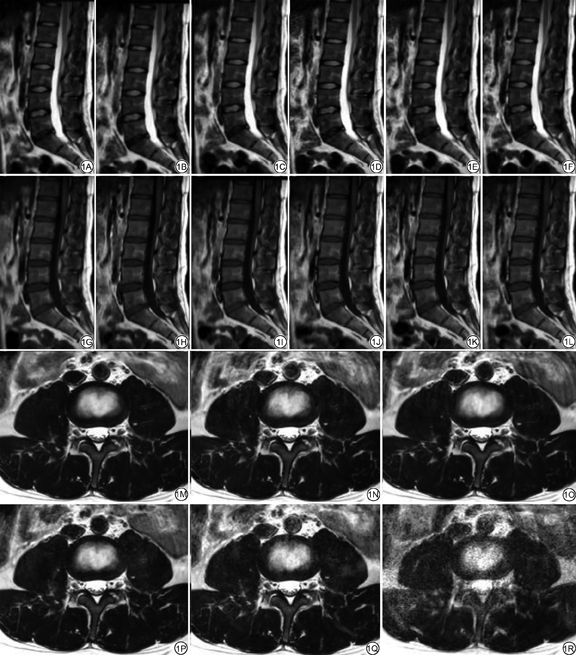

使用Philips Ingenia CX 3.0 T MRI(Philips Healthcare, Best, the Netherlands)设备,12通道内置体线圈。所有被试均行常规和5种不同AF的腰椎矢状位TSE-T1WI和T2WI、轴位TSE-T2WI序列,具体为SENSE AF=2以及CS AF=2、3、4、5(图1)。(1)矢状位T1WI扫描参数:TR 324 ms,TE 9 ms,体素0.89 mm×2.01 mm×4.00 mm,层间距1 mm,信号平均采集次数(number of signal average, NSA)1,无加速、SENSE 2、CS 2、CS 3、CS 4、CS 5扫描时间分别为162.0 s、84.0 s、84.0 s、58.3 s、45.4 s、37.6 s;(2)矢状位T2WI扫描参数:TR 1600 ms,TE 90 ms,体素0.80 mm×1.83 mm×4.00 mm,层间距1 mm,NSA 1,无加速、SENSE 2、CS 2、CS 3、CS 4、CS 5扫描时间分别为103.0 s、51.3 s、51.3 s、35.2 s、25.6 s、22.4 s;(3)轴位T2WI扫描参数:TR 3200 ms,TE 129 ms,体素0.60 mm×0.95 mm×4.00 mm,层间距0.4 mm,NSA 2,无加速、SENSE 2、CS 2、CS 3、CS 4、CS 5扫描时间分别为216.0 s、115.0 s、115.0 s、76.0 s、64.0 s、50.9 s。

ANOVA检验矢状位TSE-T1WI、T2WI、轴位TSE-T2WI不同AF间椎体和间盘的SNR、CNR及主观评分差异有统计学意义(P<0.05;表3)。两两比较结果:当CS=4时,矢状位T1WI椎体和间盘的SNR、矢状位T2WI椎体和间盘的SNR、CNR和主观评分较常规序列差异有统计学意义(P<0.05);当CS=3时,轴位T2WI椎体SNR较常规序列差异有统计学意义(P<0.05;图3)。

本研究将CS应用于2D腰椎矢状位T1WI、T2WI和轴位T2WI三个序列,优化AF。结果表明当AF为3、3、2时,椎体SNR、CNR和主观评分与常规序列差异无统计学意义,扫描时间缩短56.65%,扫描效率提高一倍以上,相关研究国内尚未有报道。通过CS使腰椎MRI时间显著缩短,不仅可以提高检查成功率,还可提高设备的社会经济效益,具有较好的临床应用前景。

常规腰椎MRI检查包括矢状位T1WI、T2WI和轴位T2WI三个序列,一次检查时间约10 min,已成为临床最常见的检查之一。但对于部分受检者,因慢性腰背疼等原因难以忍受长时间检查,缩短扫描时间可以有效提高检查成功率。BRATKE等[35]将CS与腰椎3D-T2WI序列结合,结果表明当应用AF=4.5时,扫描时间缩短39%,图像质量与应用SENSE的序列无明显差异。MORITA等[12]将CS应用于腰椎3D-T2WI-VISTA序列,可以在保证图像质量的前提下明显缩短扫描时间。然而,由于3D序列扫描时间相对较长,2D序列在临床的应用更加广泛。所以本研究将CS与腰椎2D MRI序列相结合,探究CS对2D腰椎MRI图像的影响,以推广其临床应用价值。BRATKE等[13]将CS应用于腰椎矢状位2D TSE-T2WI与GRE-T2WI序列扫描,结果表明TSE序列较GRE序列伪影减少,且可以使用更高的AF。对于TSE序列,AF为3时图像质量满足诊断需求,扫描时间缩短43%。本研究根据前者的研究,创新性地将CS应用于腰椎矢状位T1WI、T2WI和轴位T2WI三个序列。当AF为3时,矢状位T2WI序列椎体、间盘SNR、CNR和主观评分与常规序列无明显差异,扫描时间缩短65.83%(103.0 s vs. 35.2 s),与前者研究结果一致,但节省了更多的扫描时间。对于矢状位T1WI和轴位T2WI序列,AF分别为3和2时,扫描时间缩短64.01%(162.0 vs. 58.3 s)、46.76%(216.0 vs. 115.0 s),且对陈旧性椎体压缩骨折、许莫氏结节、腰间盘突出、椎体脂肪化等腰椎退行性病变显示良好,图像质量满足诊断需求。

综上所述,对比传统序列,结合CS的腰椎2D序列可以在保证图像质量的前提下,有效缩短扫描时间,提高检查成功率。临床推荐AF分别为3、3、2行腰椎矢状位T1WI、T2WI和轴位T2WI序列扫描,对腰间盘突出、陈旧性椎体压缩骨折等退行性病变显示清晰,部分新发压缩骨折患者、严重脊椎后凸患者也可配合完成检查。且总扫描时间缩短56.65%,扫描效率提高一倍以上,可以显著提高MR设备的社会经济效益,减少患者预约等待时间,具有一定的推广应用价值。